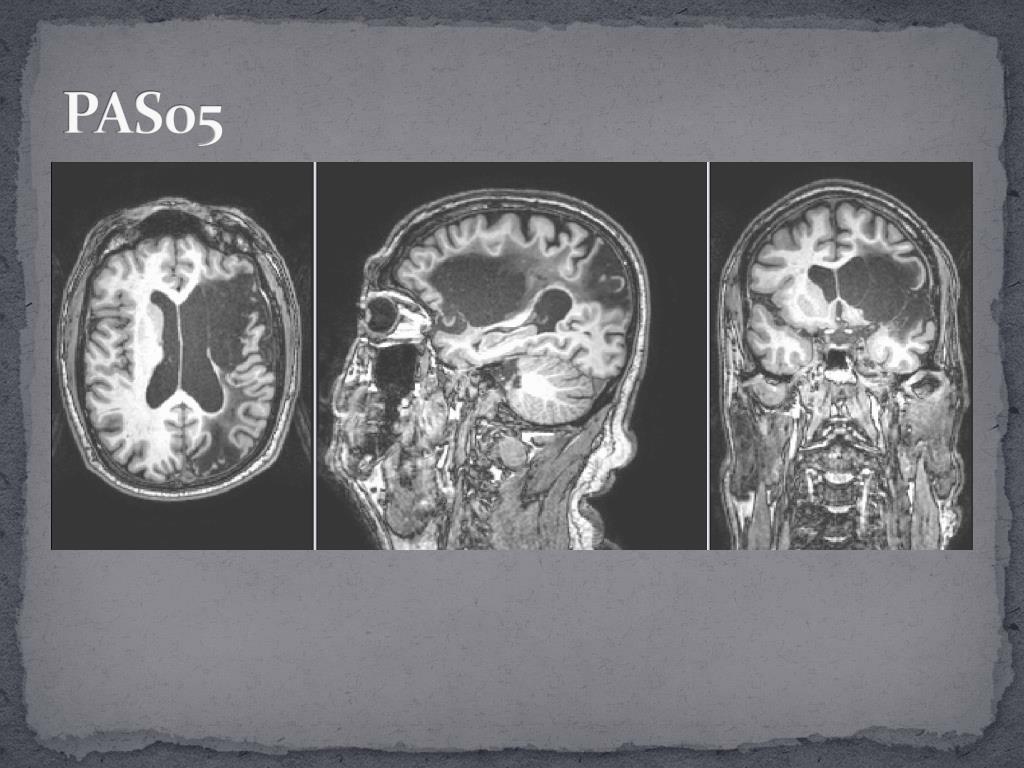

15. Participants • T1 MRI showed left hemisphere infarction.

20. PAS05